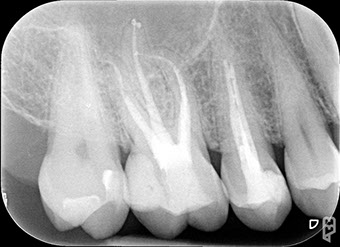

All'esame radiografico, sia l'Ascesso che il Granuloma sono rappresentati da  un'area di ridotta densità ossea, visibile come un'areola scura in prossimità dell'apice radicolare.